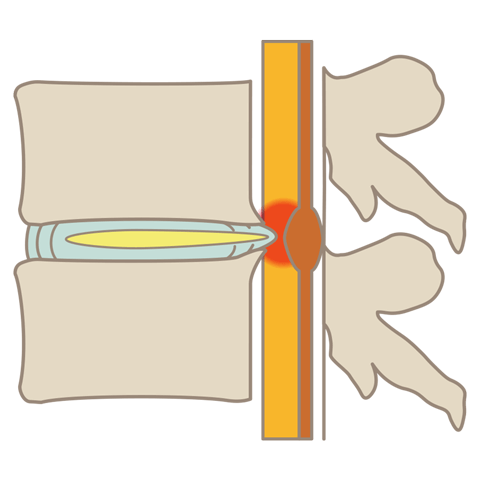

腰のMRI検査ですが、複数か所で椎間板が損傷しております。椎間板容量も50%以下であることから、減圧治療(PLDDやセルゲル治療)は適応外であると判断し、ディスクシール治療をお勧めしました。

椎間板検査(Annulogram検査)を行っているところになります。繊維輪の損傷が確認され、予定通りディスクシール治療を行っています。

腰椎椎間板ヘルニアとは、背骨の間にある椎間板(ついかんばん)が外に飛び出し、神経を圧迫する疾患です。坐骨神経痛やぎっくり腰などの症状を引き起こします。

腰部脊柱管狭窄症とは、背骨にある神経の通り道「脊柱管」が狭くなる疾患です。腰痛や足の神経障害、歩行困難などの症状を引き起こします。